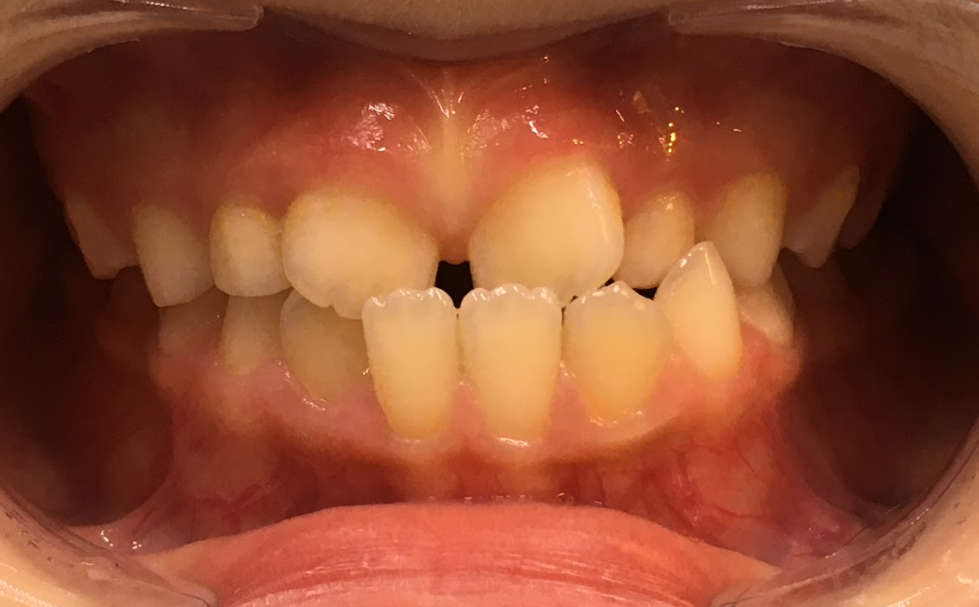

小児矯正(Ⅰ期治療)により交叉咬合および歯列不正を改善した症例(8歳女児)

治療前 ![]() |

歯並びが気になることと、歯が交差して生えていることを心配され来院されました。見た目だけでなく、噛み合わせへの影響も不安に感じておられました。 |

| カウンセリング・診断結果 |

上下前歯部に叢生傾向が認められ、加えて一部に交叉咬合が確認されました。歯列弓の幅が不足しており、このまま永久歯が萌出すると叢生の悪化や咬合のズレが進行する可能性がある状態でした。 |